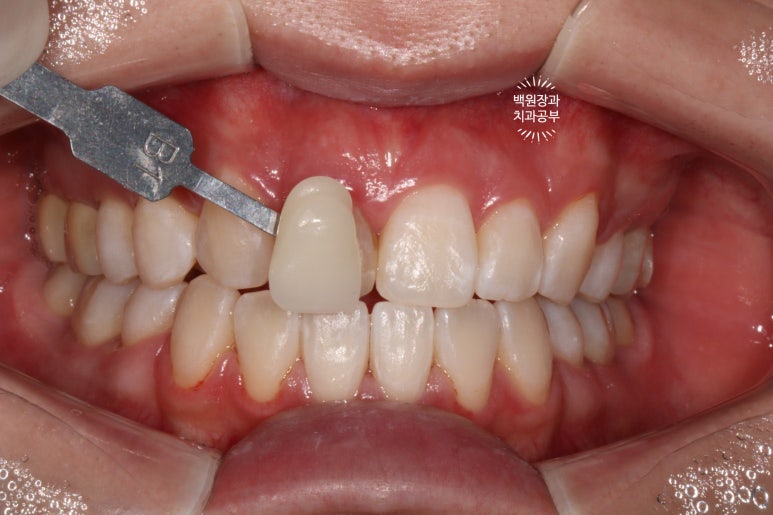

B1임을 측정해서 임시치아를 제작해 붙인채로 약 1달 정도 기다리면 좋습니다!

지르코니아 크라운을 제작하였습니다.

최대한 비슷한 형태로 반대쪽 치아와 유사하게 지르코니아 크라운을 제작해드렸습니다.

새 크라운이라 조금 더 윤이 나고 반짝반짝하지만, 환자분은 매우 만족해 하셨어요!